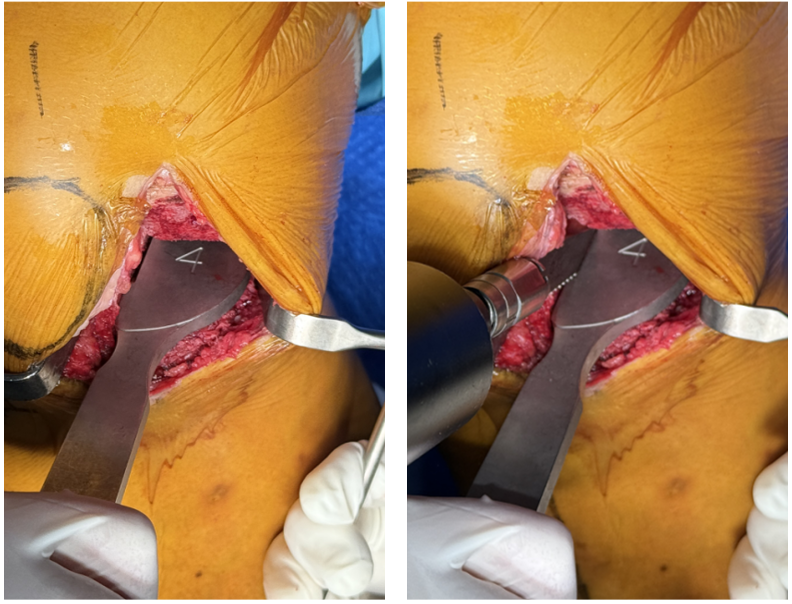

三、手术视频

2、胫骨平台半脱位,标记胫骨截骨线

-

一把Hoffman经过髁间窝插入胫骨平台后侧,将胫骨平台前脱位,充分显露骨平台;

标记胫骨截骨宽度: 从 PCL 附着点的内侧开始向前延伸,经过胫骨棘突内侧,最后延伸至胫骨结节内侧的三分之一;

标记胫骨截骨厚度: 在胫骨平台中央磨损最低点下方4-5mm处。